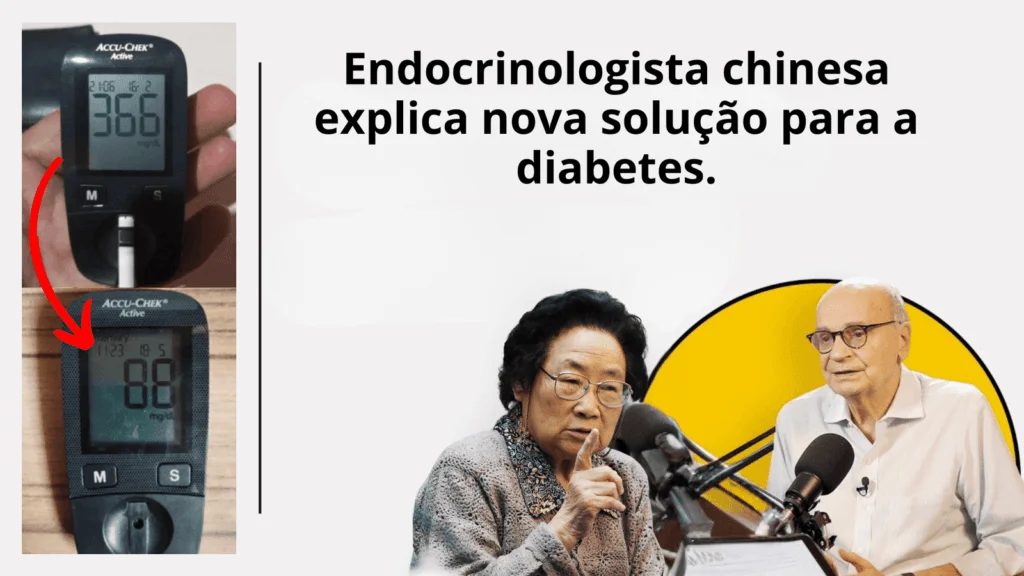

Endocrinologista revela a verdade sobre medicamentos convencionais e mostra como manter a glicemia abaixo de 100 mg/dL – de forma natural e segura

Este suco especial atua diretamente eliminando a gordura no pâncreas, permitindo que o corpo retome a produção natural de insulina e fazendo com que a taxa de açúcar no sangue volte para os níveis saudáveis (de 400 para 100 mg/dL).

“Eu sou a Luzinete Lima e passei 15 anos lutando com minha glicemia, que sempre estava acima de 400 mg/dl. A preocupação com minha saúde era constante e eu vivia com medo do futuro.

Mas, três meses depois de começar a usar o BIOGOTA, minha realidade começou a mudar drasticamente. Consegui estabilizar minha glicemia para 94 mg/dL além de perder 8 kg de gordura localizada.